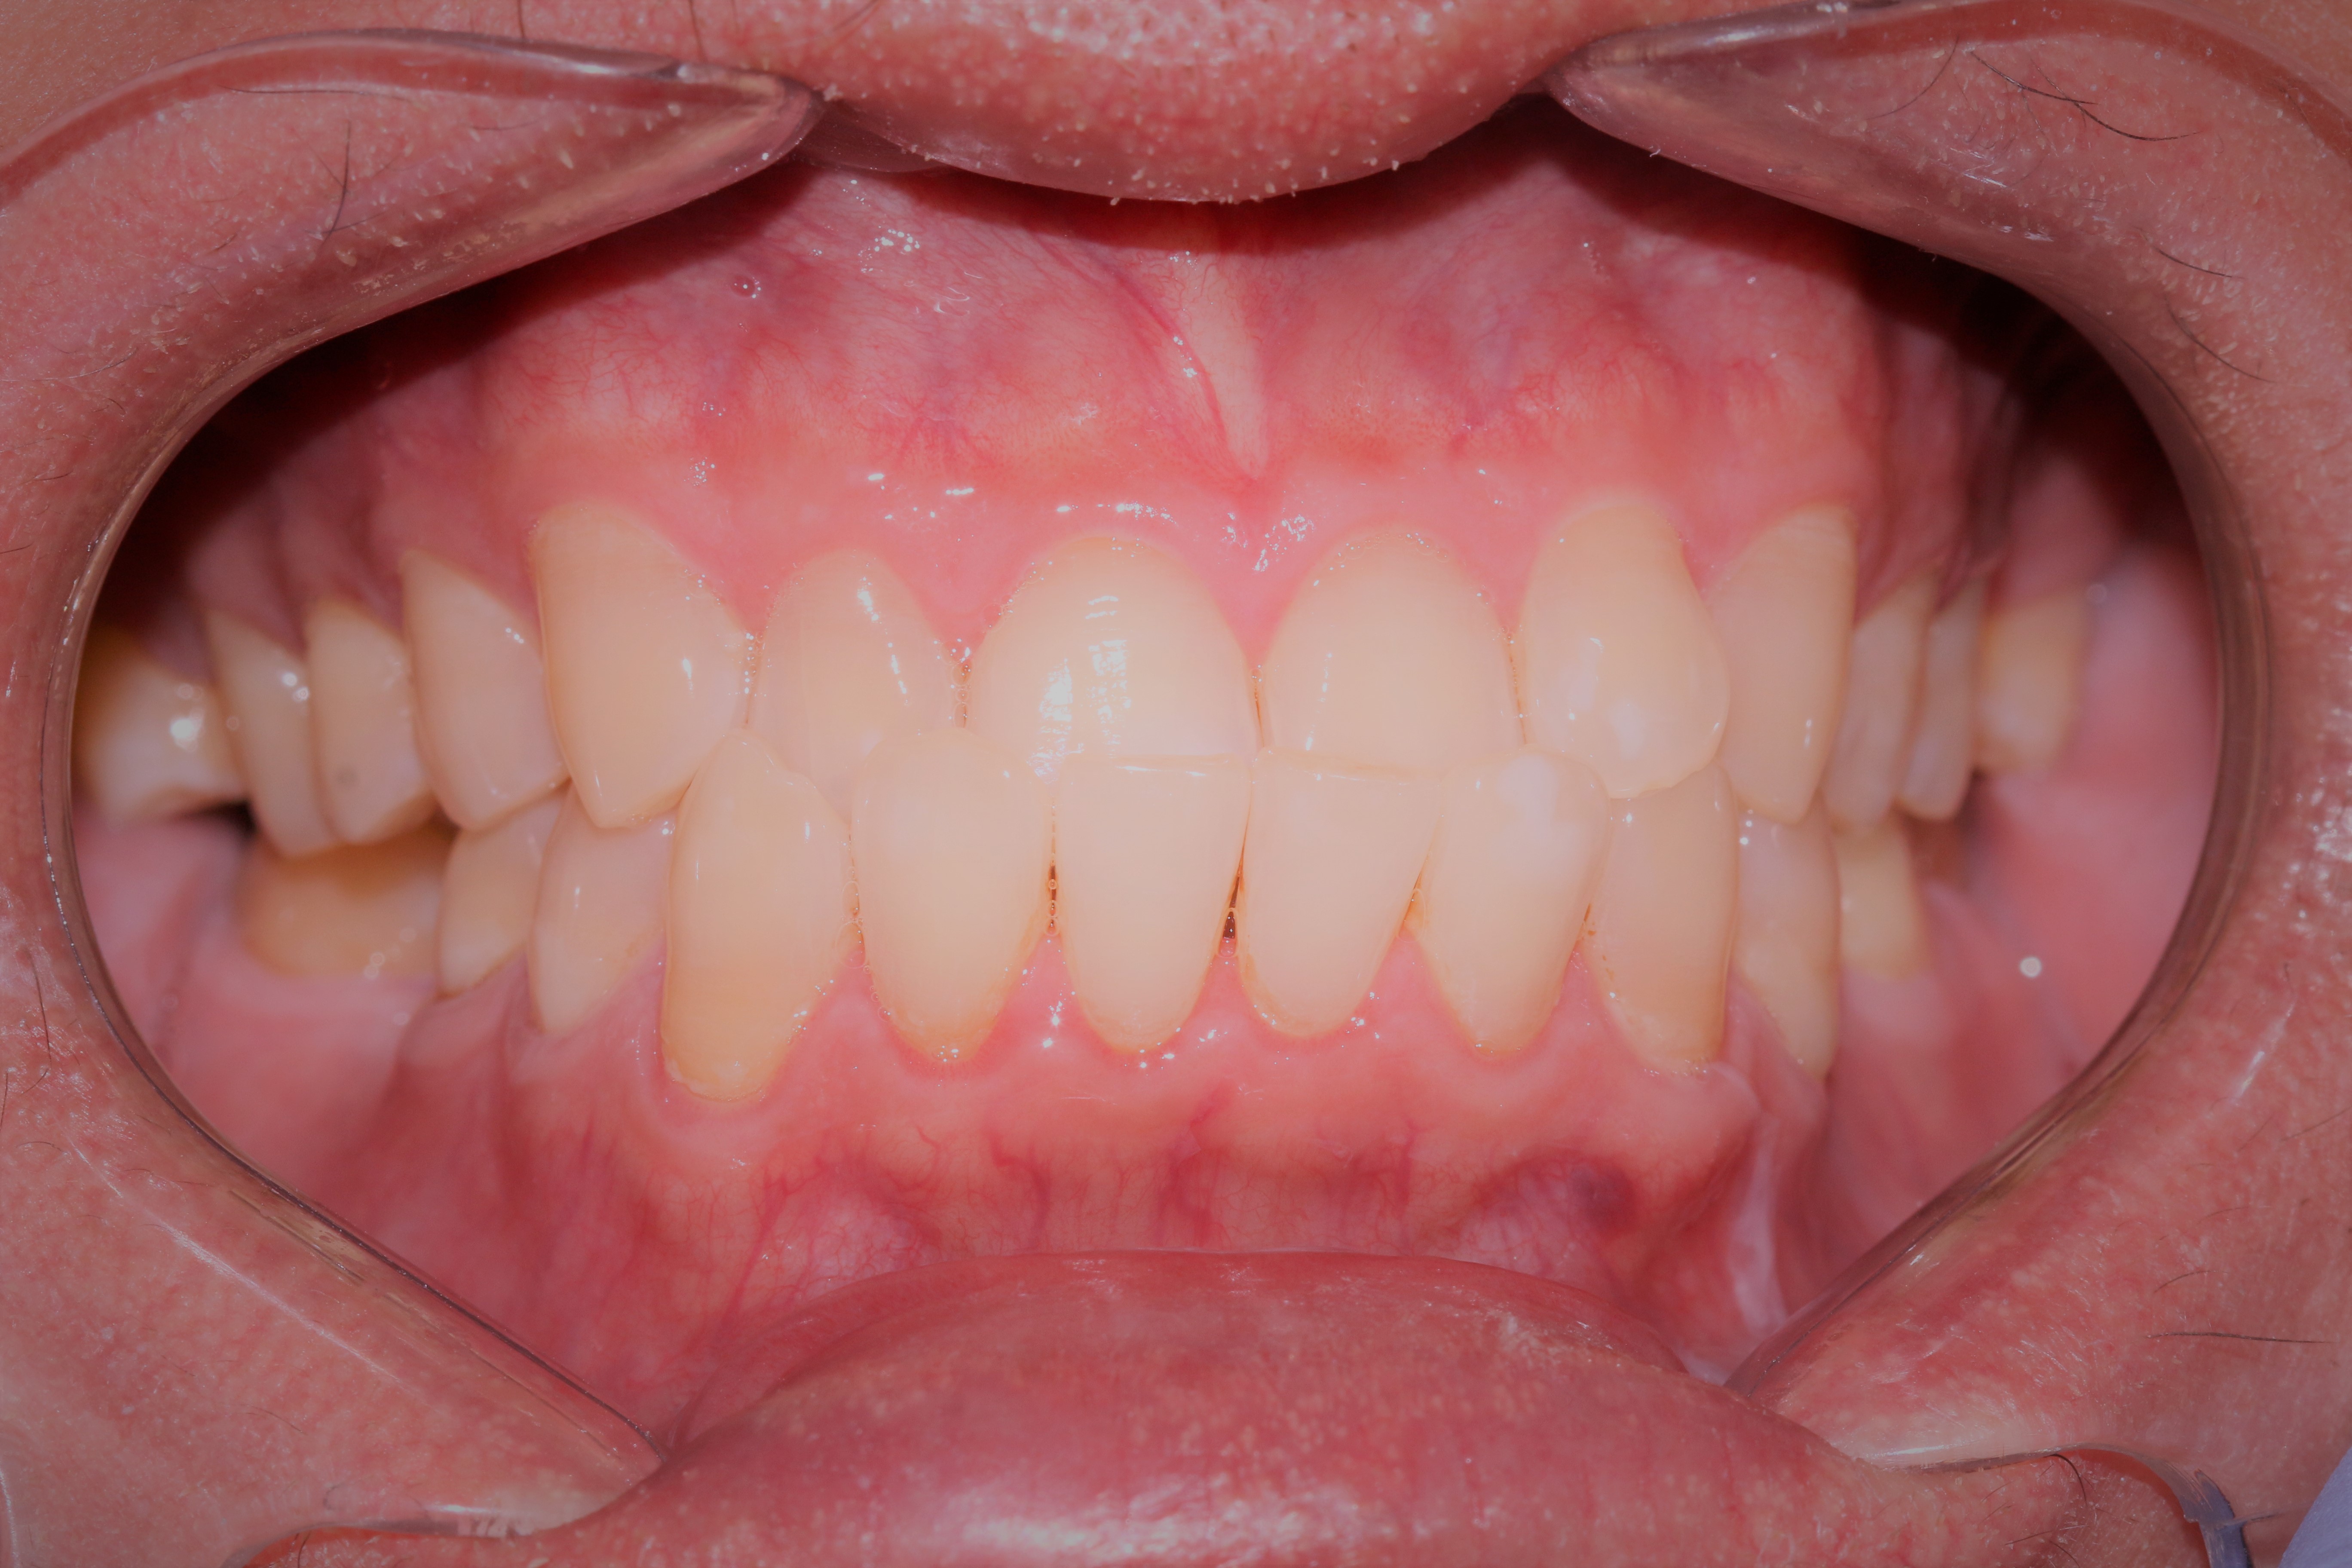

(Left) From a distance, my smile before seems ok, which appears to have even set of teeth, but if you take a closer look (right), you will notice the underbite/crossbite

Before and After Smile